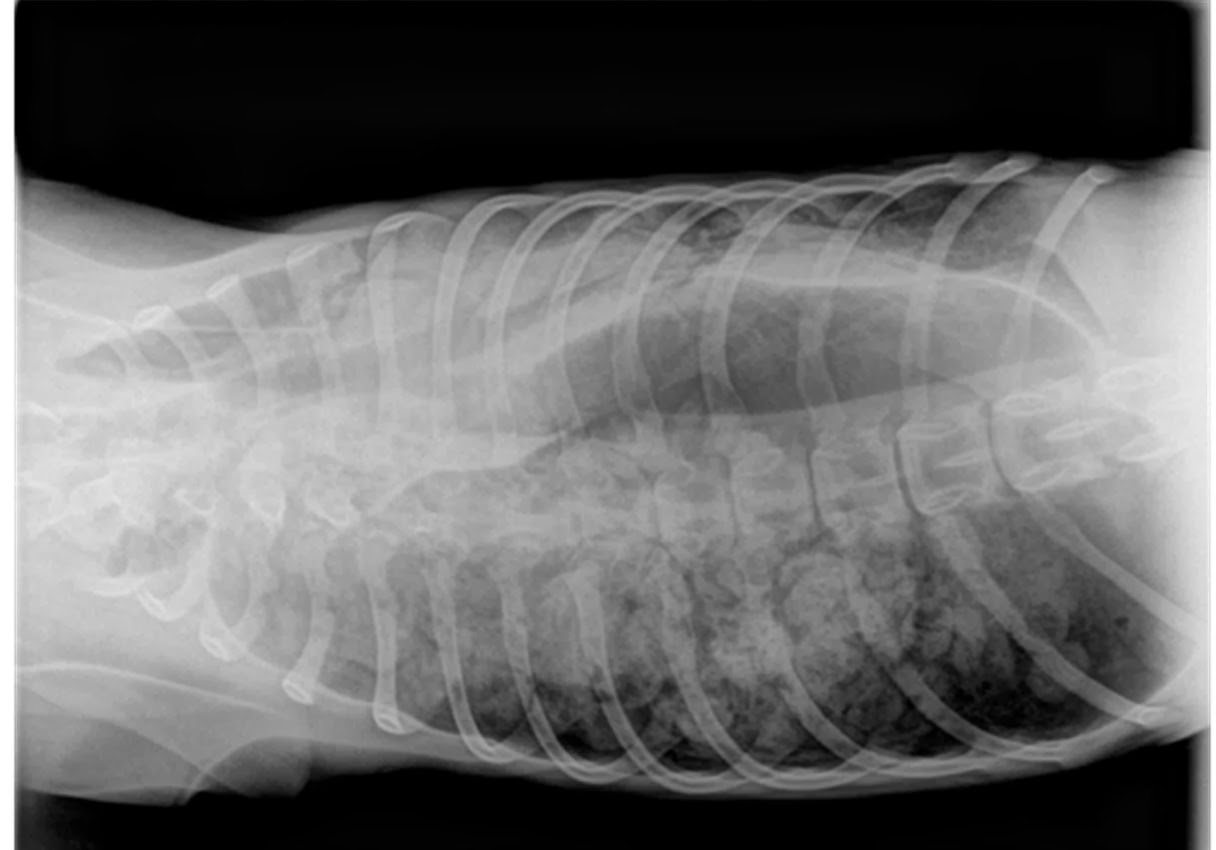

WebEn los caninos, el cáncer de pulmón primario, un tumor que se encuentra en los pulmones, es relativamente infrecuente. Oír el diagnóstico del veterinario de cáncer. WebDiagnóstico y tratamiento del edema pulmonar en perros. Se utilizan pruebas diagnósticas como la auscultación, la radiografía de tórax o la ecografía,. WebComúnmente produce metástasis en los pulmones, empeorando gravemente la situación. Por ello, debemos acudir al veterinario en caso de notar bultos. WebSeguimos con las enfermedades cardíacas congénitas de nuestros perros. Hoy hablamos sobre la estenosis pulmonar. Tenéis más información en nuestra página www... WebCausas del edema pulmonar en perros. Muy a menudo se tiende a asociar al edema pulmonar con la neumonía, pero esta no es la única causa posible. La verdad es que. WebMi perro tiene parásitos pulmonares. Junto a estos parásitos más conocidos hay otros que no lo son tanto, como es el caso del Angiostrongylus vasorum, nematodo. WebCualquier tipo de cáncer puede conducir a metástasis. Más a menudo, las metástasis se producen en el hígado, los pulmones y los huesos. Las metástasis comienzan a.

WebSíntomas en perros de edema pulmonar. En general, en un perro con edema pulmonar vamos a poder identificar síntomas como los siguientes, que se. WebLos tumores más comunes que originan metástasis a los pulmones son el cáncer de colon, cáncer de mama, los sarcomas óseos y de partes blandas, el melanoma y los tumores.

WebCualquier tipo de cáncer puede conducir a metástasis. Más a menudo, las metástasis se producen en el hígado, los pulmones y los huesos. Las metástasis comienzan a. WebDiagnóstico. Una vez en la clínica veterinaria, a nuestro perro le harán una radiografía y, si hay sospecha de cáncer, se le realizará además una citología, que es el estudio de las.